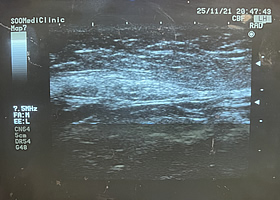

초음파

3D 입체 초음파로 피부, 피하지방층, 근육, 신경 등 연부 조직의 위치와 두께 측정